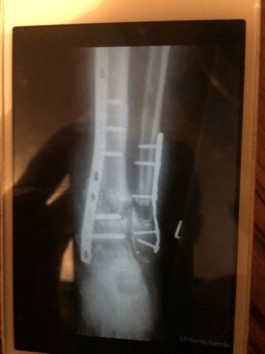

Über eineinhalb Jahre hat Cora Straßburg Ahmad Houmsi auf dem Weg von seiner neuen Wohnung in seine alte Flüchtlingsunterkunft begleitet. Die eine möchte er nicht bewohnen, solange seine Frau nicht bei ihm ist, in der anderen findet er Gemeinschaft und neue Freunde. Immer wieder erzählt Ahmad Houmsi aus seinem früheren Leben. Er spricht von seiner Zeit als Profifußballer und zeigt stolz Fotos, die er bis nach Deutschland rettete, damit die Menschen ihm Glauben schenken. In seiner Heimatstadt Aleppo war er als Schiedsrichter, Bademeister, Feuerwehrmann und Vater von sieben Kindern im geselltschaftlichen Leben der Stadt fest verwurzelt, bis ein Scharfschütze sein linkes Bein schwer verletzte und er seine Heimat verließ.